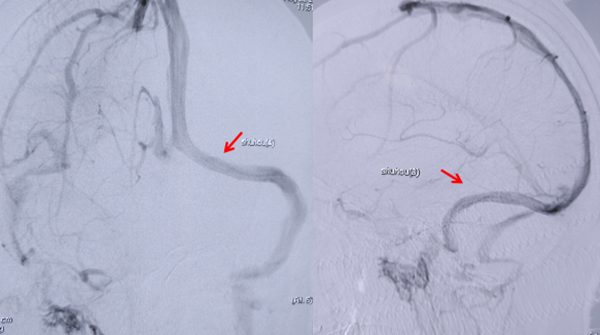

图1 术前造影发现左侧横窦狭窄(箭头处),狭窄两端压力差超过300mmH20

图2 支架植入后狭窄解除(箭头处),血流通畅,两端压力差基本消失